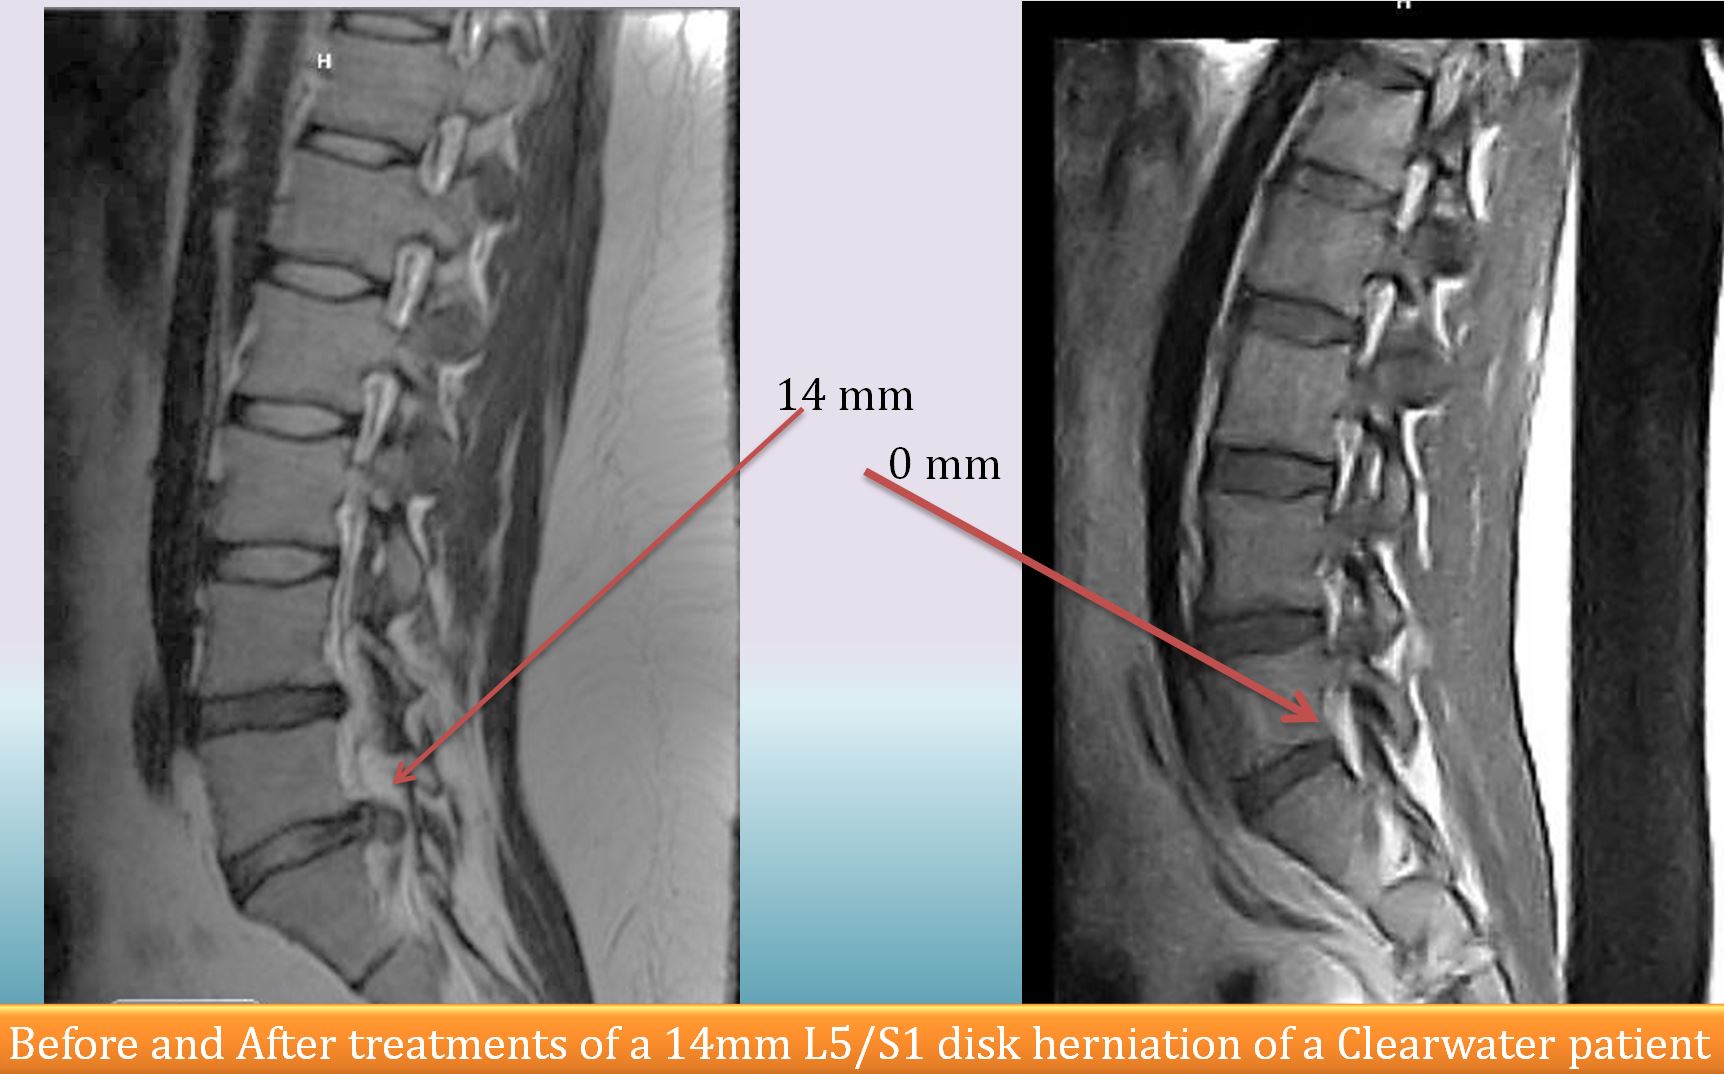

Dissolve Chronic Disk Herniations Without Open Surgery

Our proprietary injection treatments with approved drug combinations and needle placements can resolve disk herniations even as large as 14mm. Our pain center has consistently demonstrated long term pain relief in patients having chronic disk herniations after using our proprietary injection treatments thus eliminating the need for open surgery. Avoid surgery that you don’t need. Call the toll free number above or 727-474-6507 to make appointments. Our e-mail: referrals@inter-pain.com

Official reading by radiology experts conclusively demonstrated that a previously seen large disc herniation (before the treatment at Advanced Interventional Pain Center) is no longer seen (after the treatment). Call 727-474-6507 to make appointments. Our e-mail: referrals@inter-pain.com